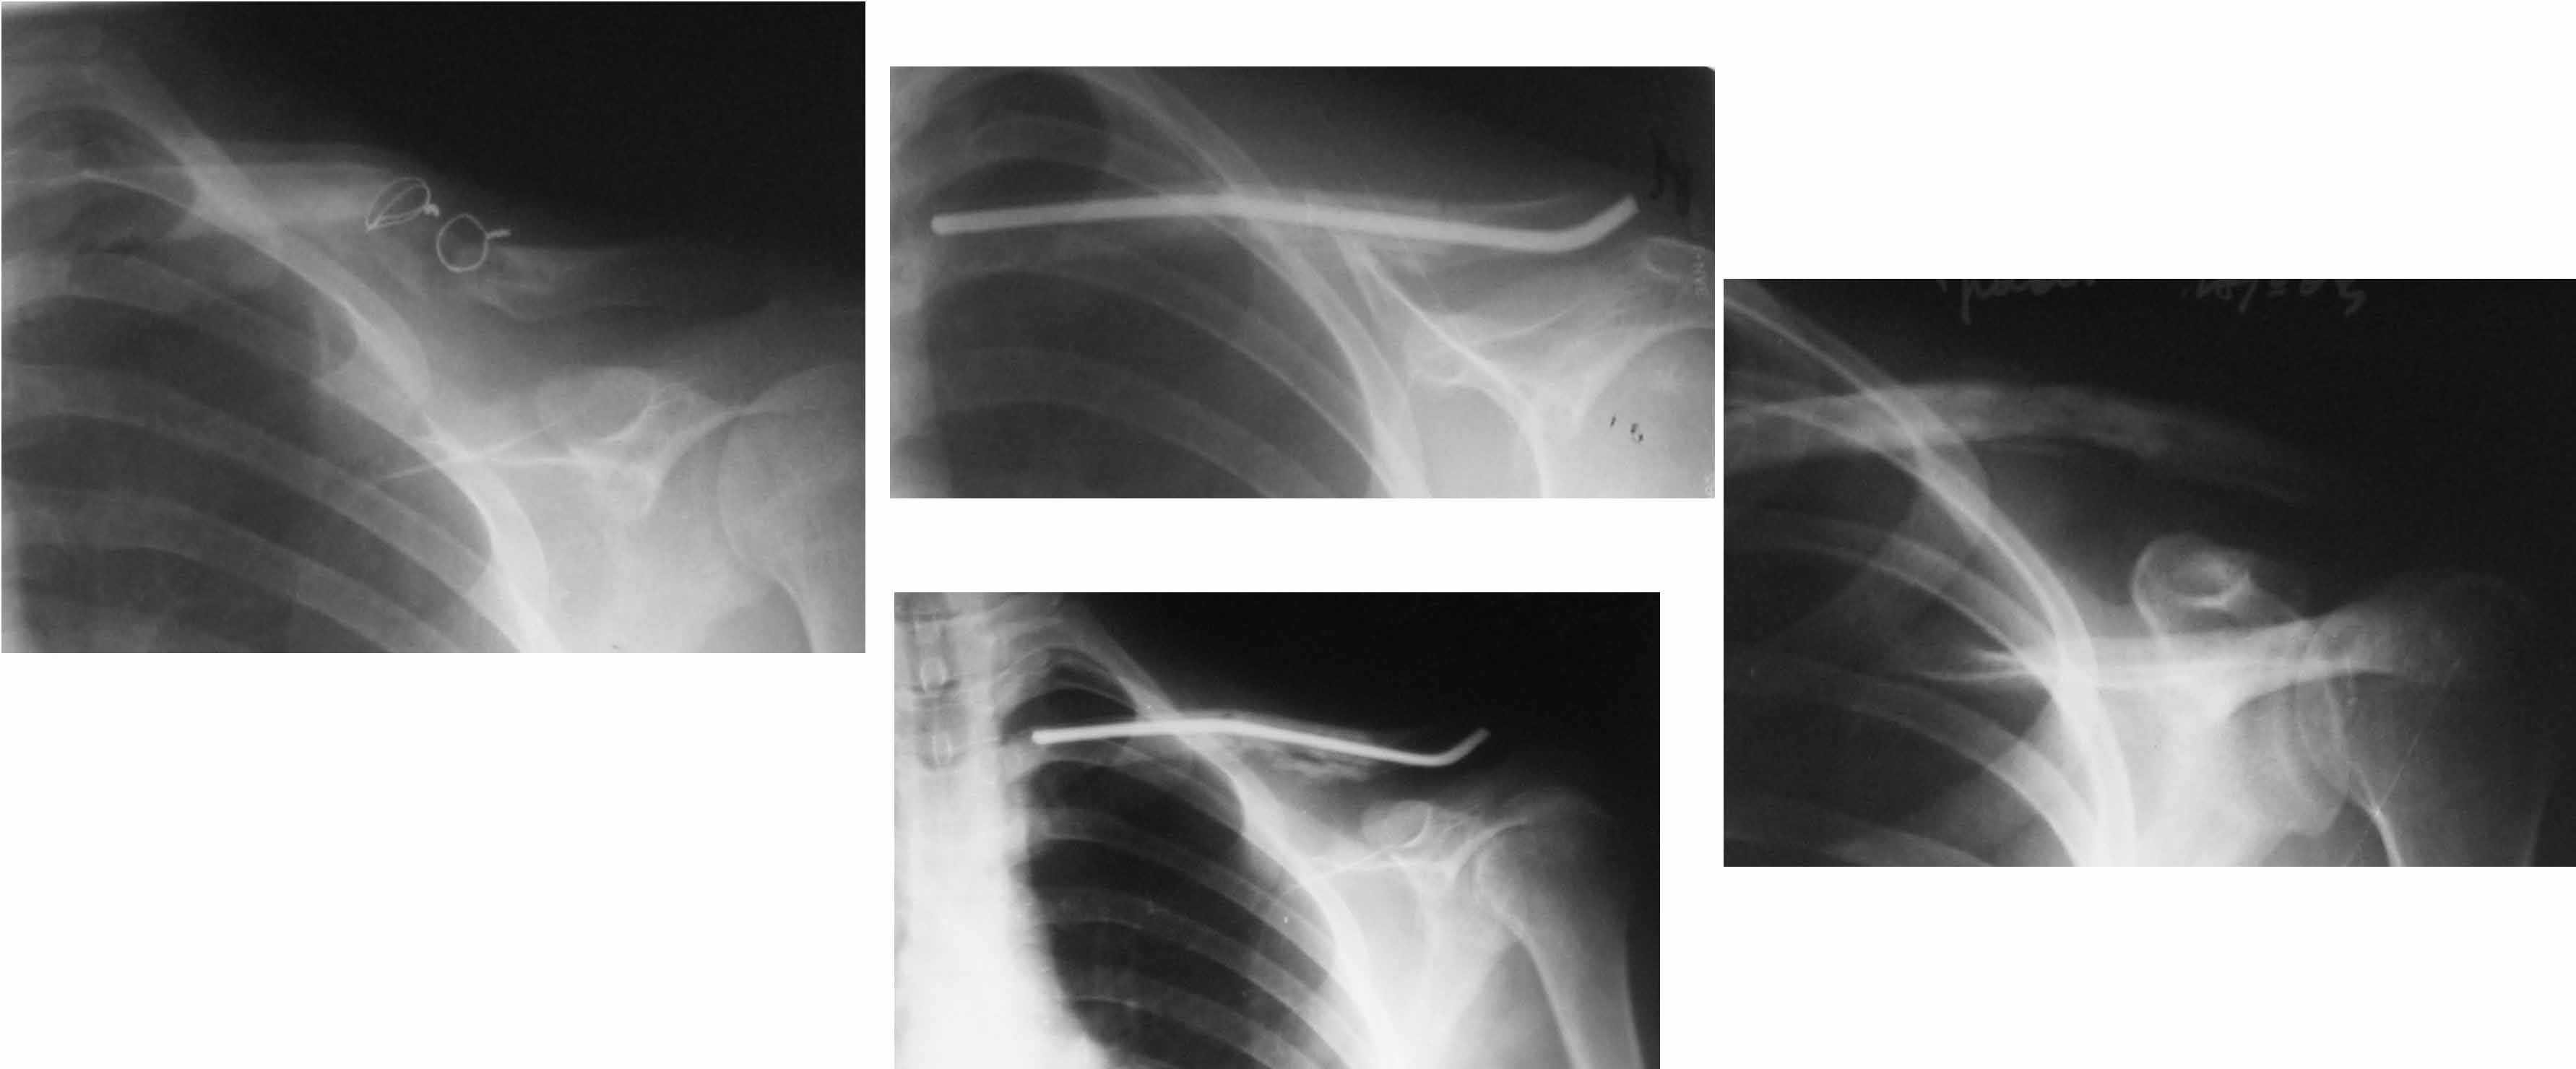

Уважаемые коллеги. Помогите с тактикой дольнейшего лечения несросшегося перелома ключицы. В отделение поступил больной, оперированный 2 мес. назад по поводу оскольчатого перелома средней трети правой ключицы. Перелом несросшийся, фиксатор несостоятелен, имеется смещение, угроза перфорации кожи. Рис. 1 Намми произведен реостеосинтез ключицы пластиной с угловой стабильностью, с замещением деффета диафиза ключицы костным аутотрансплантатом. Рис. 2 Через 5 мес. трансплантат рассосался, повторное смещение, несостоятельность импланта. Рис. 3Ваше мнение,что делать?